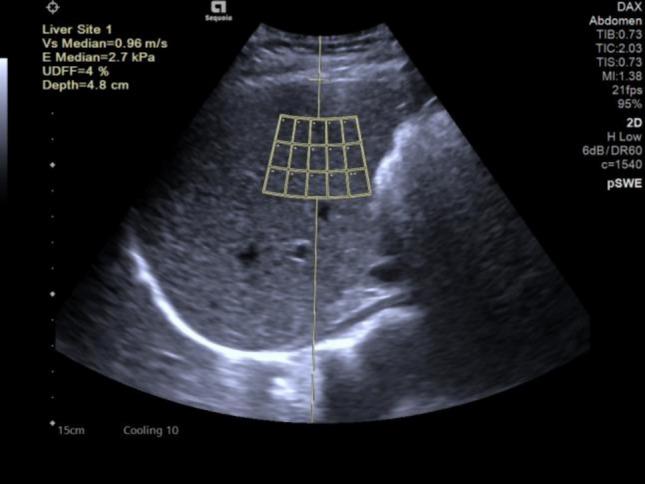

This study aims to explore the characteristics and influencing factors of ultrasound-derived fat fraction (UDFF) in obese patients with polycystic ovary syndrome (PCOS). Evaluate the diagnostic value of UDFF for MAFLD. This study included 124 obese PCOS patients and 106 age- and body mass index (BMI)-matched obese women, collecting clinical data from both groups. Compare the characteristics and related factors of hepatic steatosis between two groups. A total of 124 obese PCOS patients were divided into MAFLD group (n = 64) and no MAFLD group (n = 60). Binary logistic regression was used to analyze the independent risk factors for MAFLD in obese PCOS patients, and Spearman correlation analysis was used to examine the correlation between UDFF and various variables. The MAFLD group was further divided into mild group (S1, n = 16), moderate group (S2, n = 24), and severe group (S3, n = 24). Based on the ultrasound results, draw a receiver operating characteristic curve (ROC) for diagnosing the degree of hepatic steatosis in obese PCOS patients using UDFF. MAFLD was more common in the obese PCOS group than in the simple obese group (51.61% vs. 40.57%, P < 0.05). UDFF is positively correlated with the severity of MAFLD (r = 0.603, P < 0.01). The AUC for diagnosing liver steatosis with S ≥ 1, S ≥ 2, and S = 3 using UDFF is 0.935, 0.951, and 0.916. UDFF has certain diagnostic value for metabolic-related fatty liver disease in obese PCOS patients, and UDFF levels gradually increase with the severity of MAFLD.

本研究旨在探讨多囊卵巢综合征(PCOS)肥胖患者超声衍生脂肪分数(UDFF)的特征及影响因素,评估UDFF对代谢相关脂肪性肝病(MAFLD)的诊断价值。本研究纳入124例肥胖PCOS患者和106例年龄及体重指数(BMI)匹配的肥胖女性,收集两组的临床资料,比较两组肝脂肪变性的特征及相关因素。124例肥胖PCOS患者共分为MAFLD组(n = 64)和非MAFLD组(n = 60)。采用二元logistic回归分析肥胖PCOS患者发生MAFLD的独立危险因素,采用Spearman相关分析检验UDFF与各变量之间的相关性。MAFLD组进一步分为轻度组(S1,n = 16)、中度组(S2,n = 24)和重度组(S3,n = 24)。根据超声结果绘制受试者工作特征曲线(ROC),以评估UDFF对肥胖PCOS患者肝脂肪变性程度的诊断价值。肥胖PCOS组MAFLD的发生率高于单纯肥胖组(51.61% 比 40.57%,P < 0.05)。UDFF与MAFLD的严重程度呈正相关(r = 0.603,P < 0.01)。使用UDFF诊断S≥1、S≥2和S = 3级肝脂肪变性的AUC分别为0.935、0.951和0.916。UDFF对肥胖PCOS患者的代谢相关脂肪性肝病具有一定的诊断价值,且UDFF水平随MAFLD严重程度的增加而逐渐升高。